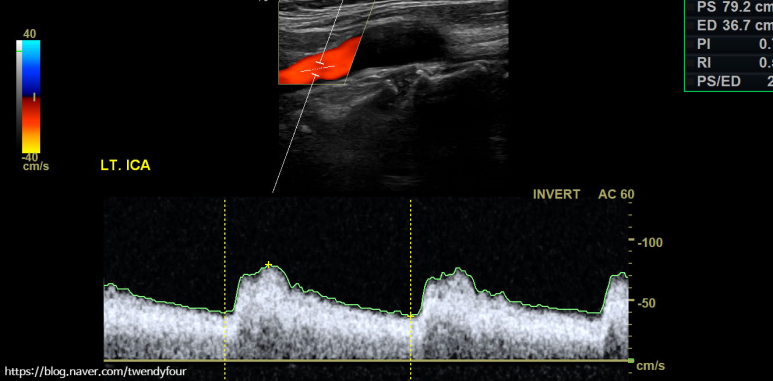

혈류 상태를 컬러로도 확인할 수 있으며, 경동맥 초음파를 정밀 도플러 검사로 혈류 속도를 측정합니다.이 검사를 통해 혈관 벽의 좁기 유무를 확인할 수 있어요.

경동맥 중의 내경동맥, 머리에 혈관의 정밀 경동맥 초음파 검사 사진입니다.

머리로의 좌측 내경동맥의 혈류속도를 확인하여 협착여부를 간접적으로 확인합니다.눈으로 얼마나 좁아졌는지도 중요하지만 사실 이 검사가 정말 중요합니다.